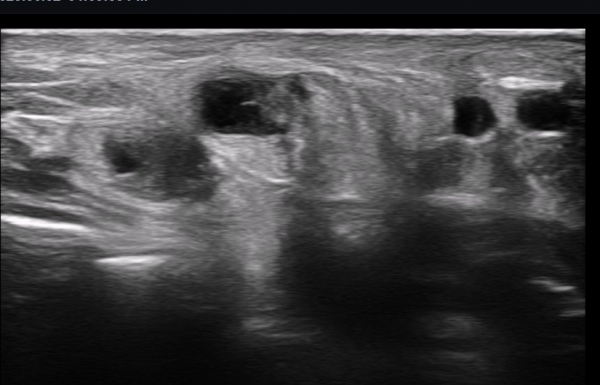

ÃÊÀ½ÆÄ ¼Ò°ß : ºñº¹½Å°æ Ⱦ´Ü¸é°Ë»ç¿¡¼­(»çÁø 1~13) ºñº¹½Å°æÀÇ Àú¿¡ÄÚ ºÎÁ¾°ú ´Üºñ°ñ°Ç³» ³¶Á¾¼º º´º¯ÀÌ °üÂûµÈ´Ù.